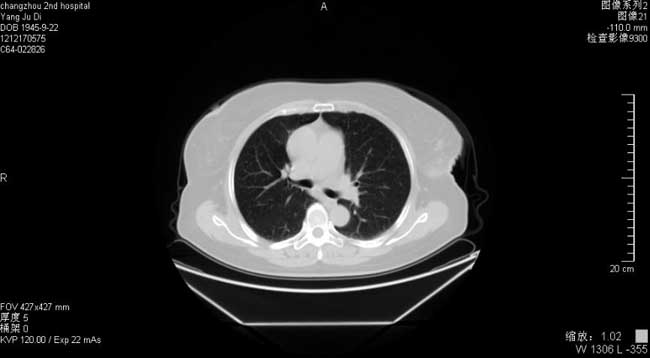

胸部CT:左侧胸壁肿块术后,两肺纹理增多,右肺下叶陈旧灶 。

胸部CT(2013-12)